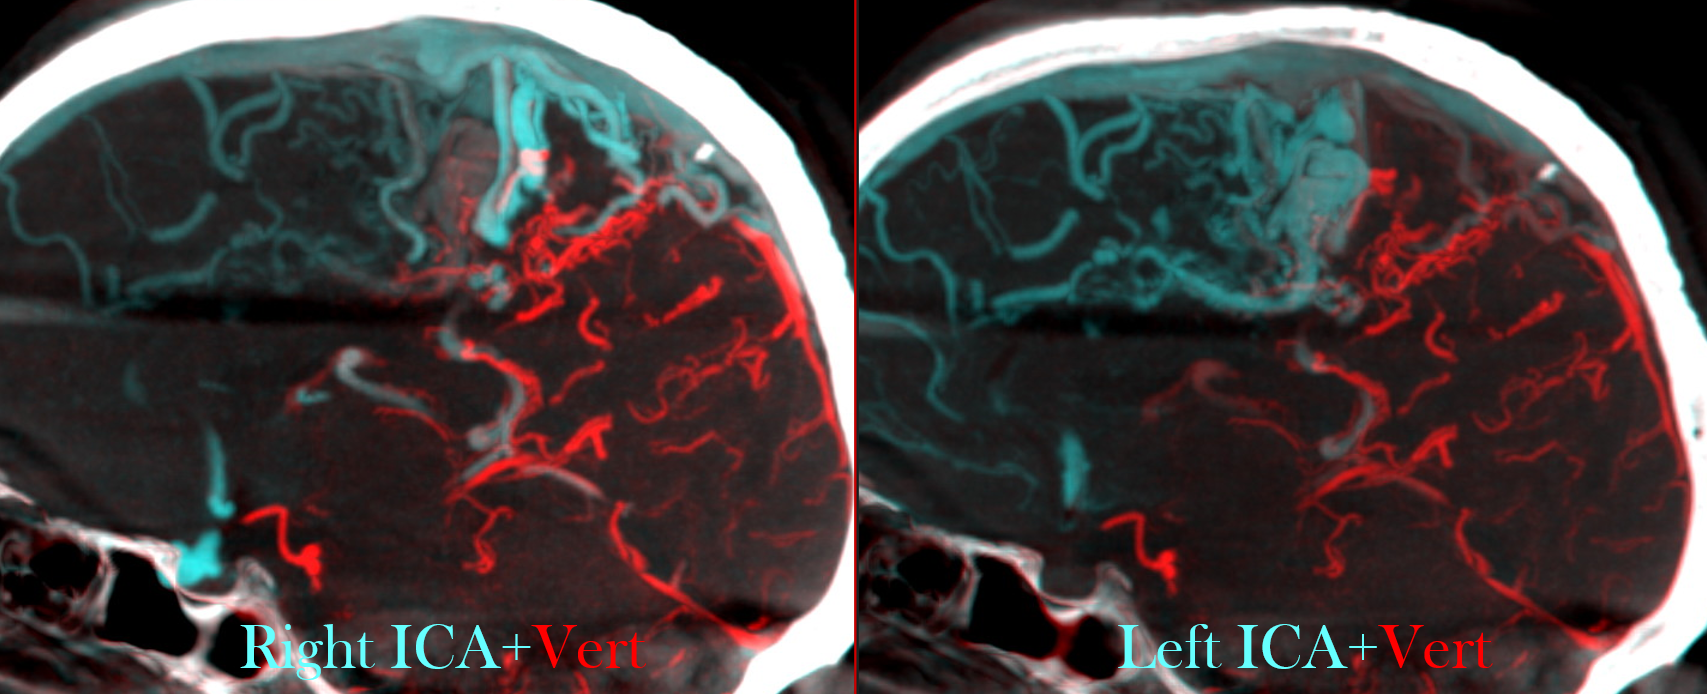

Another suer useful tool is the fusion of two different datasets (one for each AVM feeder).

First of all, open one of the two (or three, or more) datasets; then activate the fusion option and the select the dataset you want to fuse.

Then coregister the datasets; if the results are not optimal, you can manually improve the correspondence of the two datasets.

These are examples of a complex AVM. Unfortunately, we cannot save the fused datasets as a new dataset to be imported in the GammaPlan software, but just as videos.

Here we see fusion of right (blue) and left (red) ICAs in the upper line and right ICA (red) and posterior circulation (blue) in the lower line. In white you see the cast of glue injected into some large AV shunts before GK.

Although this page is not about embo technique, or outcome, or whatever multiple clinical itch questions or comments you might have, the point to be made is that gamma knife does a terrible job with macro / large intranidal shunts. If there is any chance for it to work at all, close the big shunts sub selectively and maybe some of the vein (just not the whole vein…) and gamma knife the smaller vessels which are probably not even part of the nidus to begin with… It does work better.

Note that a cyanoacrylate was used here, not EvOH. That’s why anyone who wants to attack an AVM should know how to use glue. This job is for glue.